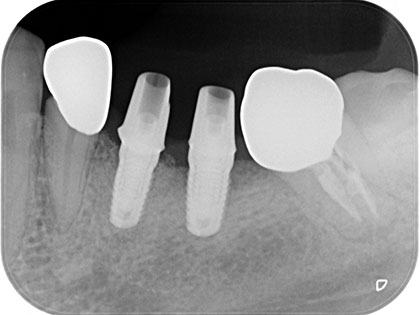

インプラント症例

左下奥歯6、7番目にインプラント治療を行った症例

左下が腫れたり、噛むと痛いとの事で来院され、インプラント治療を希望された患者様の症例になります